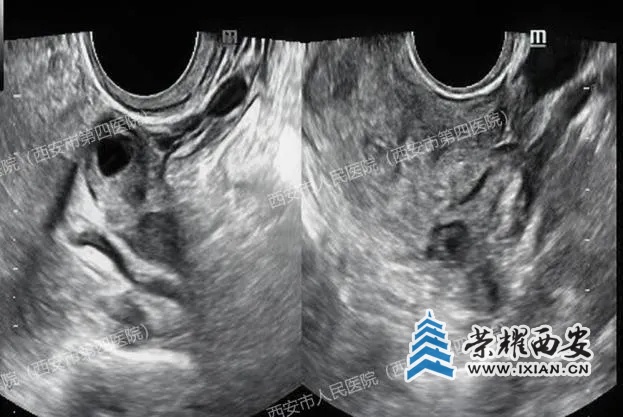

(上图腔内超声显示宫腔内未见孕囊,下图显示右侧卵巢小囊肿)

(肝右叶有一个47x35mm的囊实性占位,附件区包块影像显示为卵巢巧克力样囊肿,并非妊娠囊)

受重力影响,受精卵多种植于腹腔内偏低部位,仰卧位时,肝右叶下表面相当于腹腔最低平面,便于附着,且肝包膜、肝实质血供丰富,利于胚胎的生长发育,因此,肝脏异位妊娠多出现在肝脏右叶下表面。